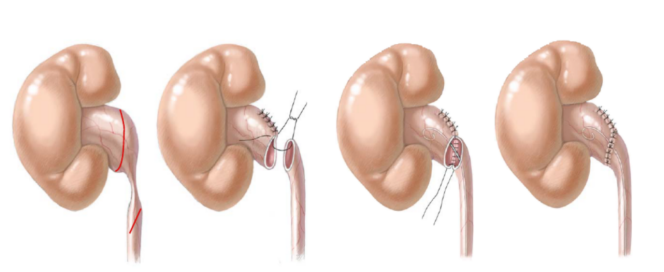

(1)输尿管狭窄段切除吻合术

适用于狭窄段较长、腔内治疗效果不佳的患者。切除狭窄段后,将输尿管断端进行吻合。

(2)开放手术

根据狭窄的部位和程度选择合适的手术切口,如腰部切口、下腹部切口等。暴露输尿管狭窄段后,进行切除吻合、再植或替代等手术。